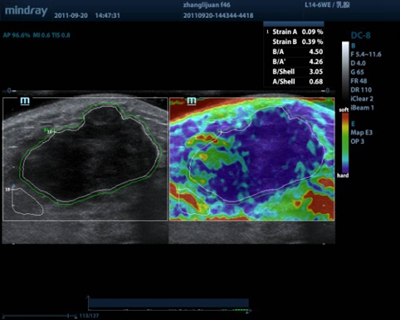

Elastograf├Ła

La funci├│n de escudo y la cuantificaci├│n de m├║ltiples par├Īmetros especiales de Mindray le proporcionar├Īn mediciones precisas sobre la rigidez del tejido. Diferencie las estructuras benignas de las malignas mediante el uso de colores distintos para codificar diferentes valores de deformaci├│n.